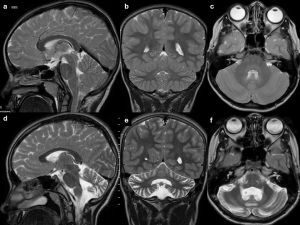

In contrast to the reversible loss of whole brain volume in patients treated with corticosteroids, another AED – phenytoin – causes cerebellar atrophy which may be irreversible, although in most cases cerebellar dysfunction regresses when phenytoin concentration is reduced (most patients with cerebellar signs have phenytoin concentrations above the reference range) [9] (Figure 1). Hyperostosis of the skull can also be observed in patients receiving phenytoin [10].

Figure 1

Drug-resistant epilepsy, responding only to high doses of phenytoin. T2-weighted images in three planes. Baseline study (top row, A-C), cerebellar atrophy on a follow-up study after 4 years (bottom row, D-F)